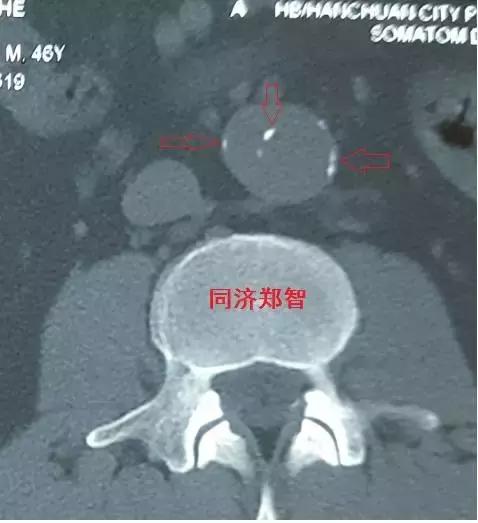

病例十

腹主动脉平扫CT提示正常外周一圈的钙化影中有内移的钙化影(红色箭头所示),CTA 证实为腹主动脉夹层。